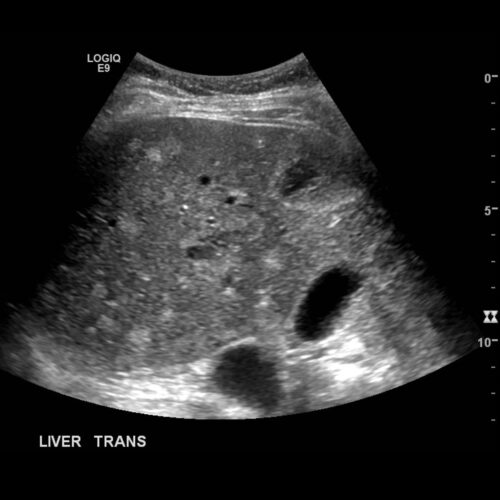

سونوگرافی کبد

رایج ترین روش تشخیص بیماری کبدی سونوگرافی کبد می باشد. روش های تشخیصی هر روز در حال پبشرفت است. بیماری کبدی همانند مرض دیابت نوعی بیماری خاموش به حساب می آید و اخیرا در جامعه بسیار شیوع پیدا کرده است.

سونوگرافی کبد اولین روش برای تشخیص بیماری های کبد، خصوصا سرطان کبد می باشد. این آزمایش با استفاده از امواج صوتی با فرکانس بالا برای ایجاد یک تصویر از یک قسمت از بدن انجام می شود. سونوگرافی کبد برای نشان دادن رشد های غیر طبیعی در کبد بیمار استفاده می شود.

اسکنر سونوگرافی دارای یک میکروفون است که امواج صوتی را خاموش می کند. امواج صوتی از اندام های داخل بدن خود، گزاف گویی می کنند در نتیجه این امواج توسط میکروفون برداشته می شوند.

میکروفون به یک رایانه وصل می شود. این موج می تواند امواج را به یک تصویر تبدیل کند. سونوگرافی کبد کاملا بدون درد برای فرد انجام می شود.

در این مرحله پزشک دستگاه سونوگرافی کبد را بر پوست بیمار فشار می دهد و آن امواج را اسکن می کند. اسکن روی صفحه نمایش ظاهر می شود.

سپس گزارش به متخصص شما ارسال می شود. اگر GP شما برای تست ارسال شود، نتایج برای جراحی فرستاده خواهد شد. سونوگرافی کبد از پنج دقیقه تا حدود نیم ساعت زمان لازم دارد. یک اسکن سونوگرافی یک روش بسیار امن است که تقریبا بدون هیچ گونه خطایی برای فرد انجام می شود.

در طی انجام سونوگرافی امواج صوتی با فرکانس بالا تصاویری از کبد شما ایجاد می کنند. این تصاویر می توانند هر گونه تغییر در کبد شما از جمله رشد سرطان را نشان دهد. افرادی که در معرض خطر ابتلا به سرطان کبد هستند، ممکن است هر 6 ماه یکبار سونوگرافی کبد به آن ها توصیه شود.